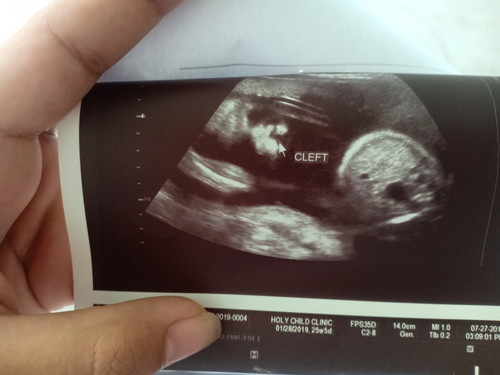

Hi mamsh, ask ko lang po may chance kayang magkamali yung ultrasound? Based on ultrasound po kasi cleft lip yung baby ko pero wala po sa lahi namin yun. Pwede po kayang mali yun?

Magbasa pailang weeks napo ba yan?? saken kase ung baby ko meron pi syang cleft lip, nung unang beses na ultra sound ko hndi pa po kase sure yon na baka may cleft lip daw po kase di masyado makita, tapos netong 38weeks pina ultra sound ko ulit meron po talaga syang cleft lip sabi nung dr. baka daw po sa lahi cause non or baka nadulas o tapilok daw p8

Magbasa paThe causes of cleft palate and cleft lip are unknown, although hereditary factors sometimes play a small role. Around one in three babies born with a cleft palate or a cleft lipmay have a relative with the same or similar condition, or an associated chromosomal or genetic condition.

😢 sana nga nagkamali lang sis. Try mo magpa CAS or ipaulit mo ultz 3d/4d kapag 30 weeks and up na si baby. Yan din ang kinatatakutan ko noon e saka lang ako nakampante nung nakapag 3d ultrasound nako. Pray lang sis 🙏

Ilang months pregnant ka na mommy? To be sure, pwede mo ask OB mo kung pwede ka na mag-undergo sa Congenital Anatomy Scan (CAS). Mas accurate kasi dun kung may physical and internal issues si baby. Pray ng pray. God bless you!